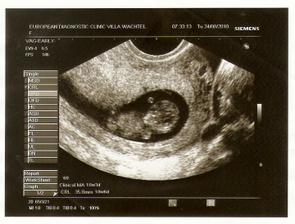

3.8.2010 (8. týden) první kontrola - miminko má 11,2 mm a krásně mu bije srdíčko... jsem moc ráda, že je všechno v pořádku